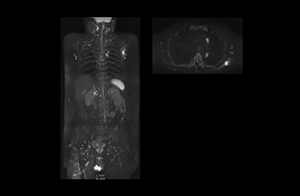

“The DWIBS sequence’s value in oncology cases is due to the high contrast it creates between lesions and surrounding tissue. Whole body DWI is requested by physicians who need to clarify TNM staging or determine therapeutic strategies, oncologists in need of diagnosis or follow-up scans, surgeons who need to see the presence of distant lesions that are sometimes difficult to detect by CT before surgery, and urologists for the evaluation of bone lesions, and the effect of chemotherapy and radiotherapy.”

“mDIXON FFE allows us to quickly get information we need to assess the presence of fat. That gives us more information when we need to diagnose bone lesions, and when we are asked to judge fat-containing lesions such as hepatocellular or renal carcinoma,” Dr. Nobusawa says. “The mDIXON fat images can help us to differentiate fatty bone marrow from bone lesions. This is especially useful in elderly people, who tend to have fattier bone marrow. The water images provide a high signal-to-noise ratio in the intestinal canal, which is valuable for visualizing lesions in the colon,” he says.

Kawasaki Sawai Hospital’s whole body protocol also includes an mDIXON FFE sequence. Because mDIXON provides images for four contrast types – water only, fat only, in-phase and out-of-phase – from a single acquisition, it is useful in many ways.